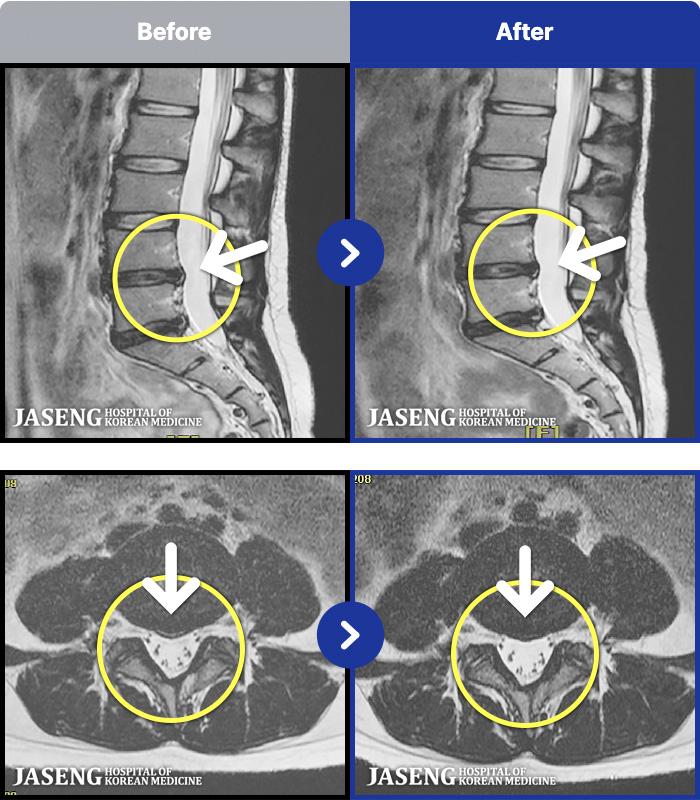

1,304 MRI ũ ʸ Ȯϼ.

[뱸] 19.11.28~25.05.06